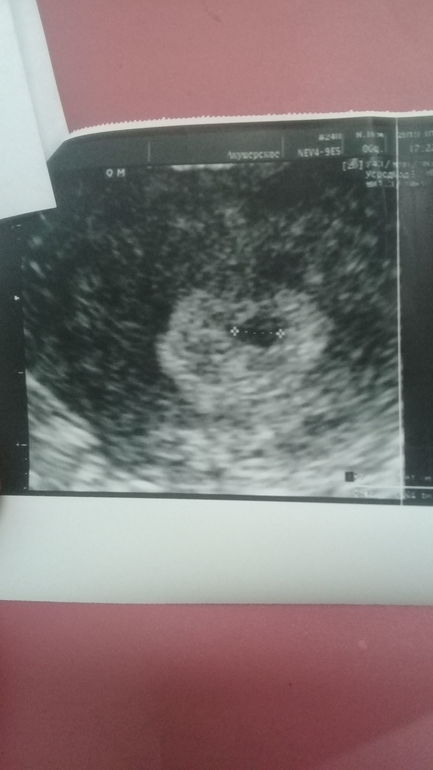

Узистка мне вы пока не радуйтесь вдруг сорвется.Тесты показывают одну полоску.У меня олигоминорея поэтому цикл 47 дней по моим подсчетам по циклу задержки нет, а если как у всех считать то задержка 4 дня.Девочки что это значит?Мне ставили поликистоз я вообще переживаю ужасно, я безумно хочу ребенка.Но почему она сказала что может сорваться и почему эти дурацкие тесты показывают одну полоску😢

Вообще непонятно, почему при ПЯ в матке и нормального размера, в моче нет ХГЧ??? Сдайте кровь и все ясно будет.

Что сказала узистка, это как гадание на кофейной гуще может да, а может нет, так что не берите в голову. А вот почему тест не показывает, а на узи пя приличного размера, это вопрос. Сдайте хгч и будет понятно. Если хгч 0 ( не Дай Бог конечно) то надо разбираться что в матке приняли за пя.